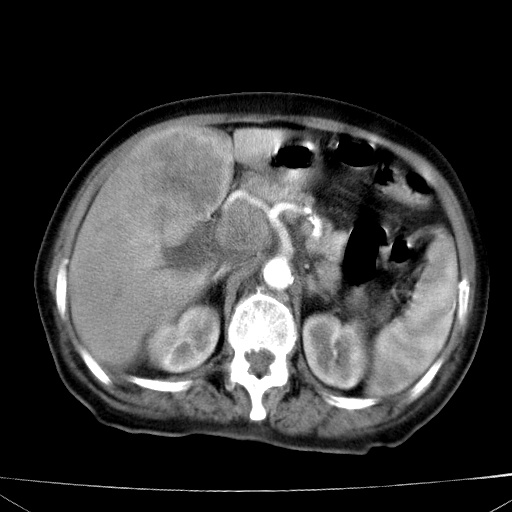

网站人气太旺!昨天的帖子就沉到海底,只好再发贴!ct18338:女 78岁,肝胆病变,已增强,再会诊!原帖链接:http://www.radida.com/bbs/forum.php?mod=viewthread&tid=50032

1)考虑胆囊癌侵犯肝脏并肝门区、腹膜后及右侧膈角后淋巴结转移。2)肝左叶近肝顶部囊肿。3)肝左叶肝内胆管结石。4)左肾近下极囊肿。